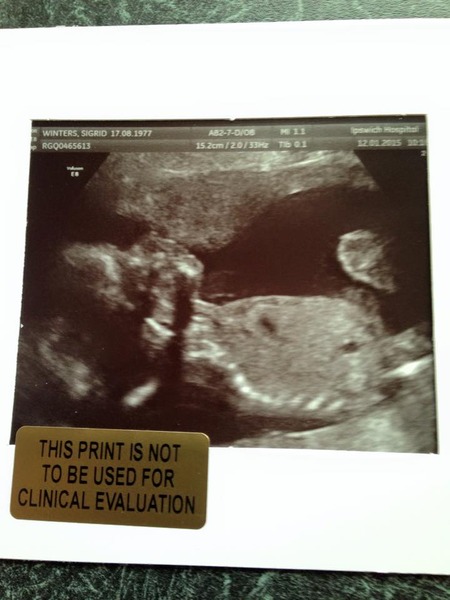

Hi All. We had our 20 week scan yesterday and after deliberation decided to find out the sex of our baby; we have two boys already. So, to our shock, apparently it's a girl! Not sure I believe it but have attached my scan photos. What do you think?

TBH the view is incomplete and I would not be able to tell from this angle.

However, the sonographer would not have said if he/she was not certain and had a good view.

Mistakes more often occur the other way round and calling a girl a boy due to placement of the cord and are very uncommon with the newer equipment,

absolutely....don't you just love that profile, looks like the baby is blowing you a kiss!